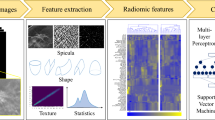

This study investigates the feasibility of using texture radiomics features extracted from mammography images to distinguish between benign and malignant breast lesions and to classify benign lesions into different categories and determine the best machine learning (ML) model to perform the tasks. Six hundred and twenty-two breast lesions from 200 retrospective patient data were segmented and analysed. Three hundred fifty radiomics features were extracted using the Standardized Environment for Radiomics Analysis (SERA) library, one of the radiomics implementations endorsed by the Image Biomarker Standardisation Initiative (IBSI). The radiomics features and selected patient characteristics were used to train selected machine learning models to classify the breast lesions. A fivefold cross-validation was used to evaluate the performance of the ML models and the top 10 most important features were identified. The random forest (RF) ensemble gave the highest accuracy (89.3%) and positive predictive value (66%) and likelihood ratio of 13.5 in categorising benign and malignant lesions. For the classification of benign lesions, the RF model again gave the highest likelihood ratio of 3.4 compared to the other models. Morphological and textural radiomics features were identified as the top 10 most important features from the random forest models. Patient age was also identified as one of the significant features in the RF model. We concluded that machine learning models trained against texture-based radiomics features and patient features give reasonable performance in differentiating benign versus malignant breast lesions. Our study also demonstrated that the radiomics-based machine learning models were able to emulate the visual assessment of mammography lesions, typically used by radiologists, leading to a better understanding of how the machine learning model arrive at their decision.